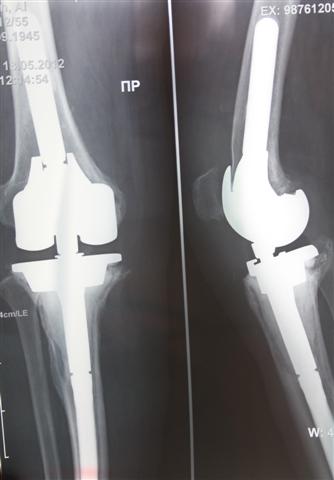

Первичное эндопротезирование коленного сустава

На сегодняшний день общепризнано, что эндопротезирование тазобедренного и коленного суставов является единственным эффективным методом лечения при разрушении суставного хряща и позволяет избавит пациента от боли и вернуть его к активной жизни. В мире ежегодно выполняется более полутора миллионов таких операций. Современные эндопротезы служат десятки лет и позволяют жить полноценной жизнью даже молодым и активным пациентам, а в случае, если эндопротез всё же износился, его можно заменить на более сложный и продолжать пользоваться всеми благами жизни.

Выполняются операции эндопротезирования тазобедренного, коленного, локтевого и плечевого суставов при онкологической костной патологии и посттравматических деформациях.